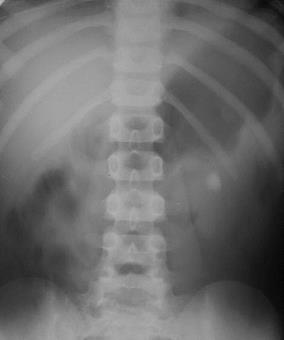

| Рис. 6.28. Экскреторная урография. Резкое расширение и деформация чашечек в правой почке. Гидронефроз правой почки. |